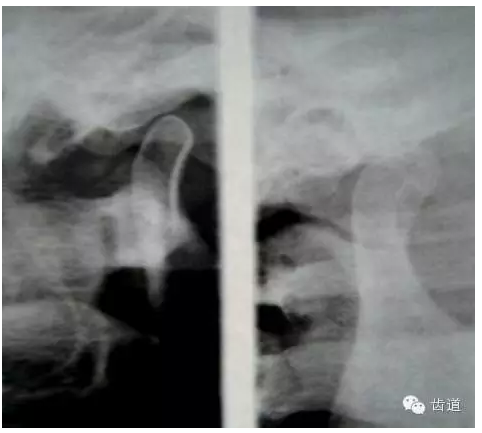

2.關(guān)節(jié)放射線平片或斷層片

— 關(guān)節(jié)間隙改變

3.關(guān)節(jié)造影 主要是上腔造影

— 顯示關(guān)節(jié)盤移位,穿孔。

4.關(guān)節(jié)內(nèi)鏡檢查-直觀

可發(fā)現(xiàn)早期病變